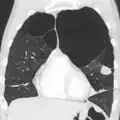

A realização de uma radiografia ao tórax e de um hemograma permitem excluir outras condições no momento do diagnóstico.[69] Os sinais característicos da DPOC observáveis em radiografia são pulmões sobre-expandidos, diafragma achatado e espaço retroesternal aumentado. Ao mesmo tempo, a radiografia permite excluir outras doenças pulmonares, como pneumonia, edema pulmonar ou pneumotórax.[70] Uma tomografia axial computorizada ao tórax permite mostrar a distribuição do enfisema pelos pulmões e pode ajudar a excluir outras doenças pulmonares.[18] No entanto, a não ser nos casos em que se planeie a realização de uma cirurgia, esta distribuição raramente influencia o tratamento.[18] Pode ainda ser realizada uma gasometria arterial para determinar a necessidade de oxigénio suplementar. Este exame é recomendado em pessoas com VEF1 inferior a 35% do previsto, com saturação periférica de oxigénio inferior a 92% e pessoas com sintomas de insuficiência cardíaca congestiva.[17] Em regiões do mundo onde é comum a deficiência de alfa-1 antitripsina, as pessoas com DPOC devem considerar a realização deste exame, sobretudo aquelas com idade inferior a 45 anos e em que o enfisema afeta a parte inferior dos pulmões.[17]

Caso grave de enfisema bolhoso

TAC axial do pulmão de uma pessoa em estado terminal de enfisema bolhoso.